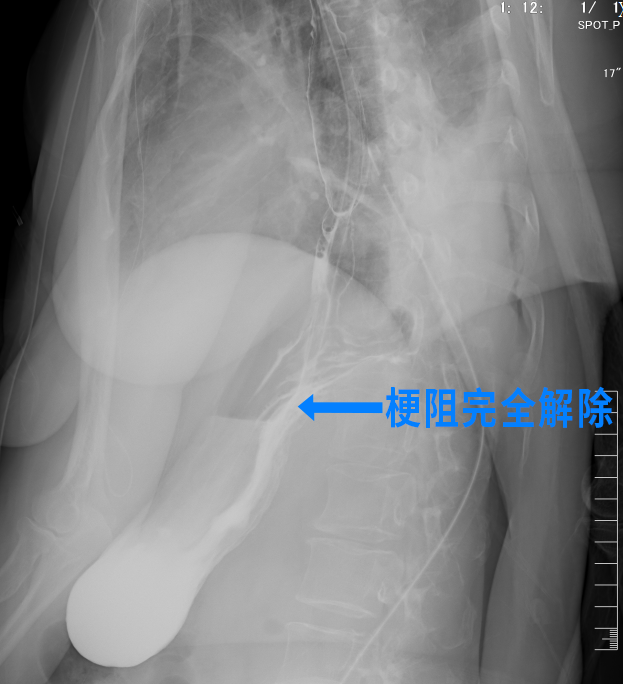

再次造影结果显示贲门梗阻完全解除,术后48小时即可进食。困扰王阿姨一年多的问题终于得以解决。

张潍教授指出:“贲门失弛缓症是食管动力障碍引发的复杂性疾病,核心矛盾是‘梗阻与反流并存’。本次手术通过多学科协作,术前优化患者身体状态,术中以微创技术实现‘切开+修补+抗反流’一体化治疗,既解除了患者的进食难题,又有效预防了术后并发症,真正实现了‘安全、精准、功能康复’的治疗目标。”